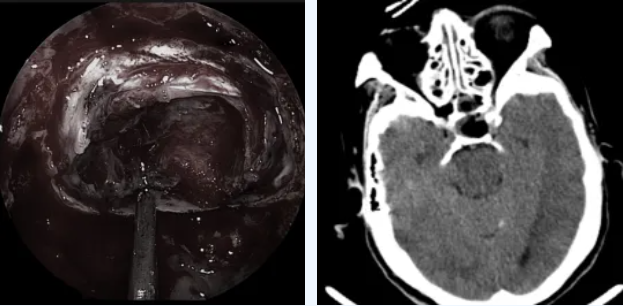

医生使用直径仅4毫米的高清神经内镜,通过鼻孔进入,手术过程清晰地显示在高清屏幕上。肿瘤被精准完整切除,完好保护了周围的神经、血管等重要结构。

肿瘤全切,术后CT未见出血

术后第二天,李奶奶就能下地行走。复查显示她的生长激素水平已降至0.931ng/mL,恢复正常范围。

神经内镜技术作为垂体瘤治疗的重大突破,提供了超清视野,让医生能够细致观察肿瘤及其周边结构,实现精准切除。对于高龄患者,这种微创手术大大降低了风险,提高了手术安全性。